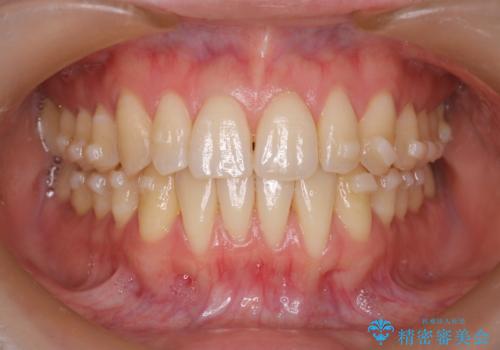

【インビザライン】反対咬合を治したい

- 前歯の反対咬合を主訴に来院されました。

インビザラインにて歯列弓の拡大により叢生の改善を行うことができ、患者様にも満足していただました。

前歯の反対咬合は歯牙への負担も大きくできるだけ早期に治療を行うことを推奨しています。